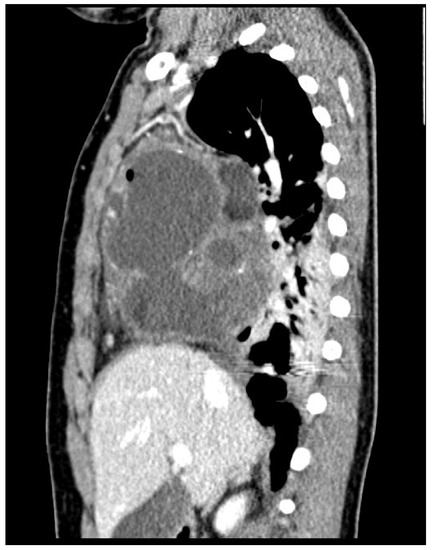

2. Case Report